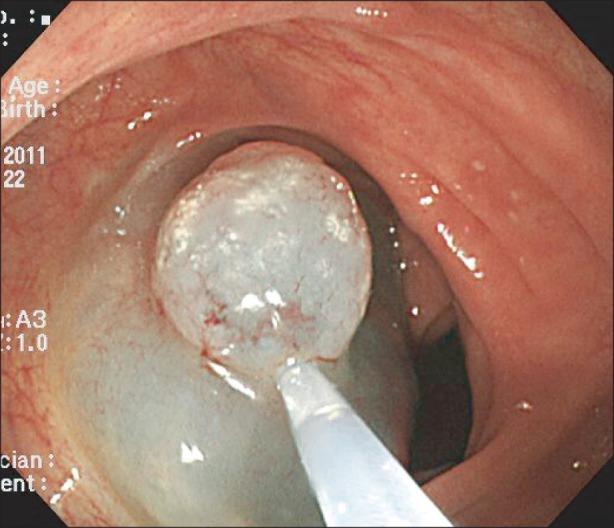

A case of ascending colonic xanthoma presenting as a lateral spreading tumor.

Gastrointestinal xanthomas are characterized by foamy cytoplasmic cells containing lipid in lamina propria, and occur almost in the gastric mucosa. Colonic xanthomas have been described in rare case. All reported colonic xanthomas were located in rectosigmoid. Rectosigmoid xanthomas have tended to exhibit small polypoid lesion, on the contrary flat in stomach. We report a case of xanthoma on ascending colon presenting as a laterally spreading tumor resected by endoscopic mucosal resection method.